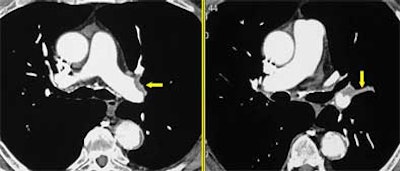

The radiologist's search for chronic PE can be boiled down to four words, Rémy-Jardin said. "The four key words are organization, calcification, recanalization -- and a very important CT finding, which is retraction of the chronically obstructed pulmonary artery," she said.

Organization: The organization of embolic material can be detected by the presence of partial or complete filling defects, Rémy-Jardin said. Unfortunately, the age of the thrombi cannot be determined by the presence of filling defects alone, so additional clues are needed to distinguish it from acute PE.

![]() |

| Organization of emblic material. All images courtesy of Dr. Martine Rémy-Jardin. |